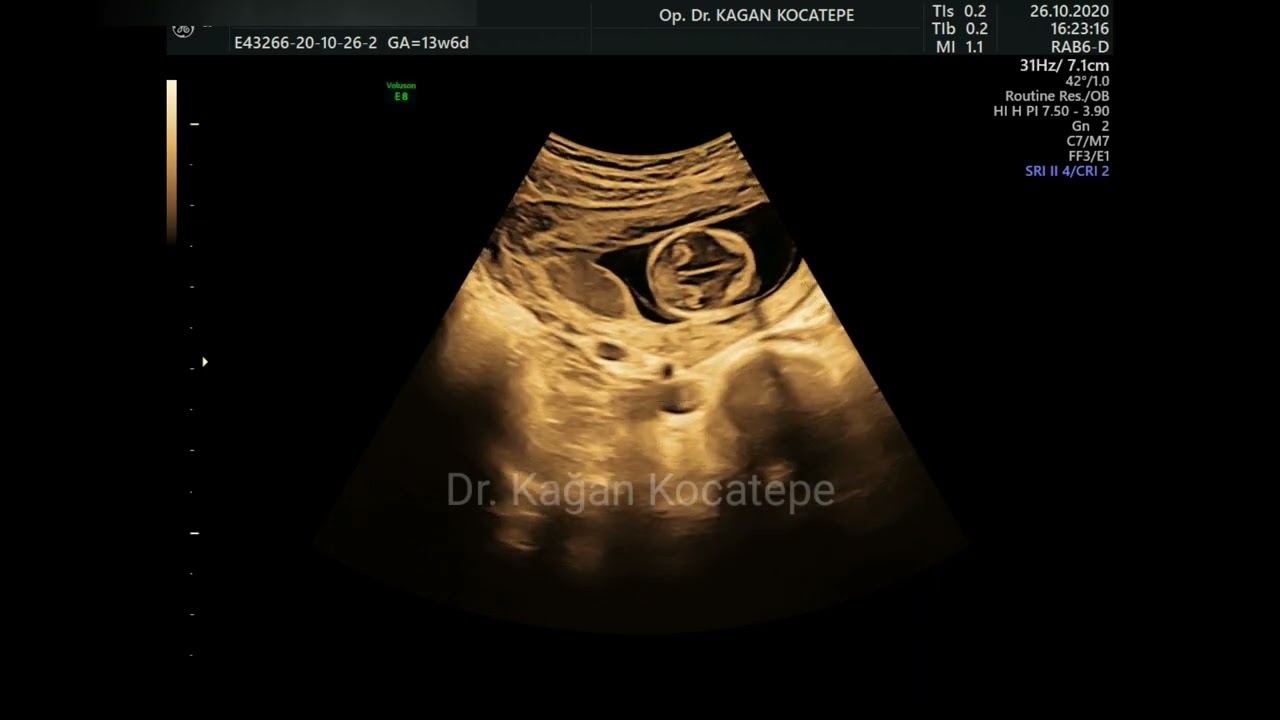

Ectopic pregnancy. Early detection and treatment options. Methotrexate, laparoscopic, open surgery

Автор: KAGAN KOCATEPE, MD, OBGYN

13+6 weeks pregnancy. Ultrasound video of a baby boy.